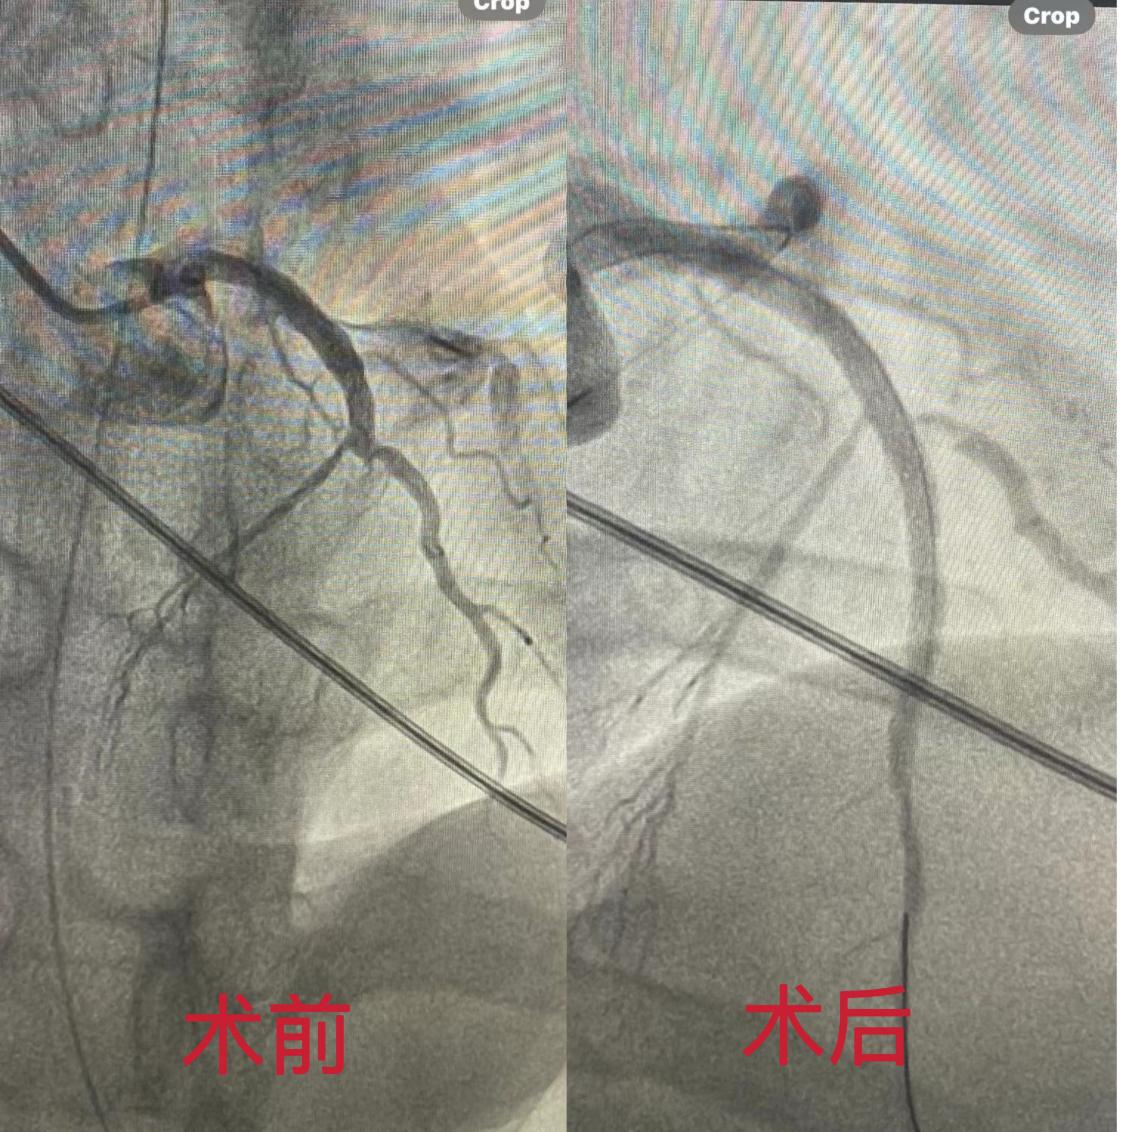

04:15患者在V-A ECMO辅助顺利转运至介入室,早已等候的心内科蒋伟副主任、杨强主治医师联合导管室护士为患者实施了急诊PCI手术,造影发现患者前降支近中段后完全闭塞,无前向血流,介入团队仅用时20分钟,就顺利开通闭塞血管并植入1枚支架,恢复了正常的血液灌流,为患者的快速康复打下坚实基础,04:50患者继续转入急诊ICU进一步治疗。